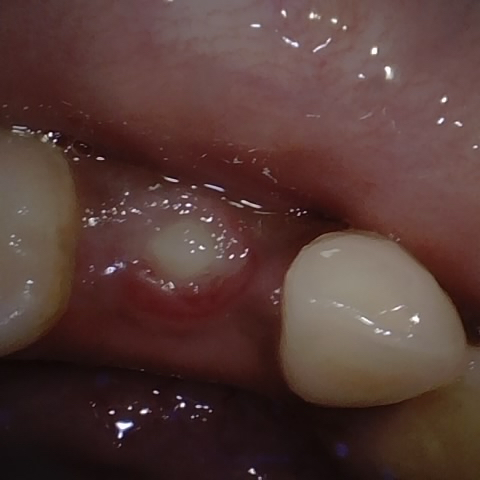

Annotated as "Good"